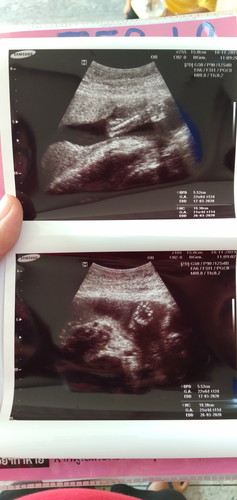

เพศลูก

ภาพนี้ซาวตั้งเเต่เดือนพฤศจิกายนวันที่18 ปีที่เเล้วค่ะ คืออยากทราบว่าเพศไร ซาวไป2รอบเเล้วหมอยังให้คำตอบไม่ได้เลยค่ะ อยากรู้เเล้วอยากเตรียมของรอ เดือนมีนาก็จะคลอดเเล้วจ้า?

แม่ซาวที่ไหนคะ โรงพยาบาลหรือคลีนิค น้องหนีบขาไว้ไม่ให้เห็นหรือป่าวคะ

แม่ลองไปซาวที่คลีนิคดูค่ะ ถ้าเป็นคลีนิคหมอจะละเอียดกว่า สงสัยอะไรถามได้หมอ โรงบาลอาจจะคนเยอะค่ะ